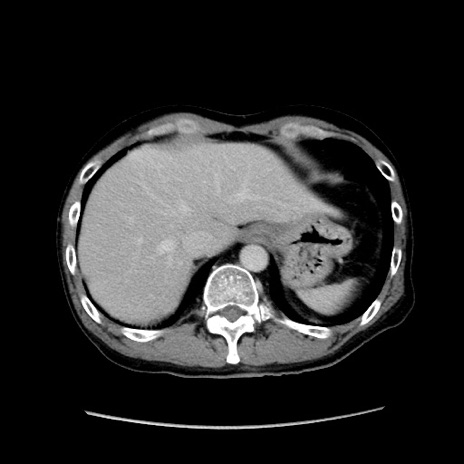

症例37(横断像)

【症例】40歳代 男性

【主訴】腹痛

【現病歴】4時間ほど前に電車に乗車中に臍部上より腹痛出現。徐々に増悪し起立困難となり、救急外来受診。生ものは数日食べていない。今朝お雑煮を食べた。

【身体所見】BT 36.8℃、BP 117/84mmHg、HR 91/min、SpO2 97%、苦悶様、腹部:臍上部広範囲圧痛あり、反跳痛±

【データ】WBC 8100、CRP 0.03